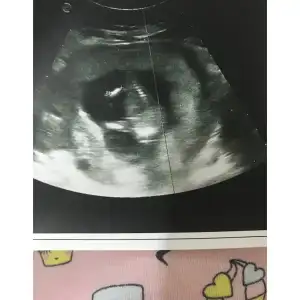

Büyüme oldu canım ama benim göğüs uclarim hiç kararmadı kızımda bunda da büyüdü ama uçları aynı kararmadı belki ten rengi açık olanlarda kararma olmuyordurKizi olan anneler hamileligin ilk ayinda gogusleriniz buyuyp kararma oldumu